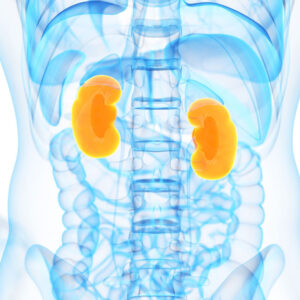

These are being an excellent book on normal home remedies for very common diseases to chronic diseases. It suggests remedies for ailments from head to toe – simple, easy-to-use, and effective.